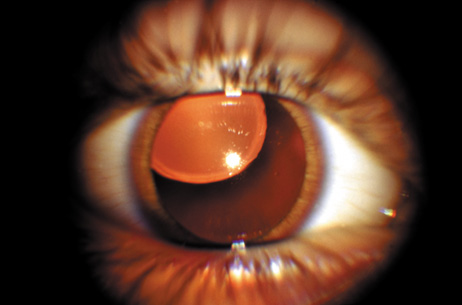

Neurofibromatosis 2 (NF2) is an autosomal-dominant (AD) disorder caused by mutations that inactivate the NF2 tumor suppressor gene. Multiple central and peripheral nervous system tumors and ocular abnormalities are common in NF2, and bilateral vestibular schwannomas (acusticus neurinoma) are pathognomonic for the disease. Constitutional nonsense or frameshift NF2 mutations are associated with severe NF2 (i.e., earlier onset of symptoms and more tumors), splice site mutations with variable disease severity, and missense mutations with mild disease. Cataracts are the most common nontumor and ocular manifestation in NF2, and are prevalent in about 60% to 80% of NF2 patients. In animal models, lens fiber cells that are more differentiated express less NF2 protein than the epithelial regions of the lens, which suggests that the NF2 protein may play a role in lens epithelial cell migration or elongation. In one study,8 the overall prevalence of cataracts in NF2 was 33%, but was significantly lower in patients with somatic mosaics and in individuals with new, as yet unknown mutations, and onset of symptoms above the age of 20 years than in patients with classic NF2, nonsense, or frameshift mutations. Of the NF2 patients with cataracts in that study, 29% were diagnosed with cataracts at an age below 10 years, and 47% were diagnosed under the age of 20 years. In 70% of the patients cataract diagnosis preceded nonocular signs or symptoms of NF2. Cataracts typically present as posterior subcapsular plaque-like opacities (Figs. 3 and 4). Other ocular manifestations include retinal hamartomas, optic nerve sheath tumors, fibrotic maculopathies, and perineural calcification of the optic nerve.9

Fig. 3. NF2. Paracentral plaque-like retrolental opacity in slit-lamp view. (Courtesy of Dr. F.D. Ellis, Zionsville, Indiana.)